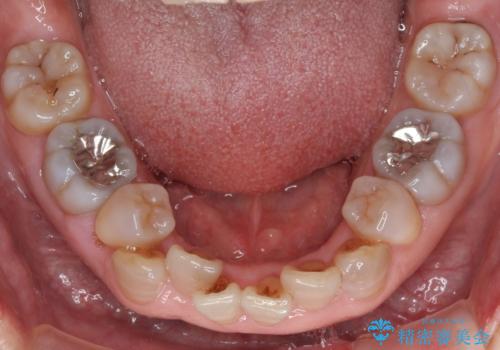

- 小さいころからの歯の変色と矯正治療の後戻りを気にして来院された患者様です。

気になる変色歯を仮歯に変え、その後歯列不正を矯正治療で改善し、最後にオールセラミッククラウンにて補綴治療することとしました。